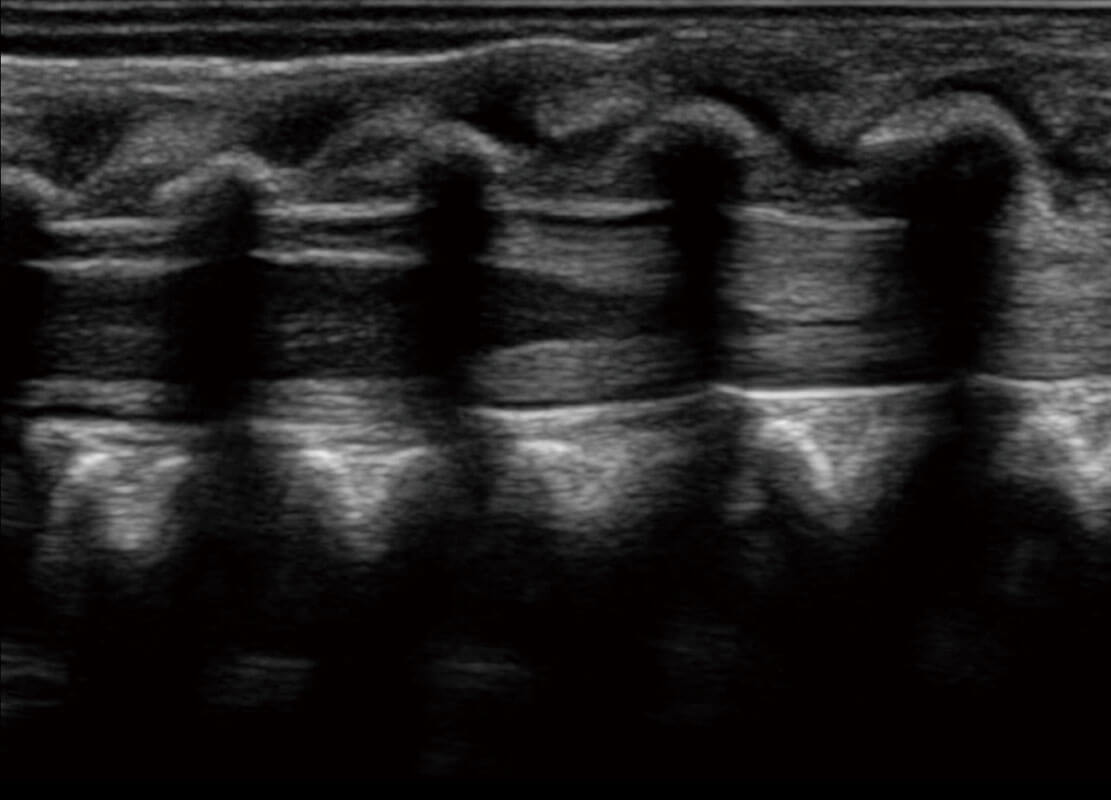

P60优异的图像质量搭载专科探头,在妇科基础疾病的诊断、卵泡生长的监测、输卵管通畅情况的判别等方面为您提供生殖应用方案。

腔内妇科-宫腔分离

腔内妇科-卵巢